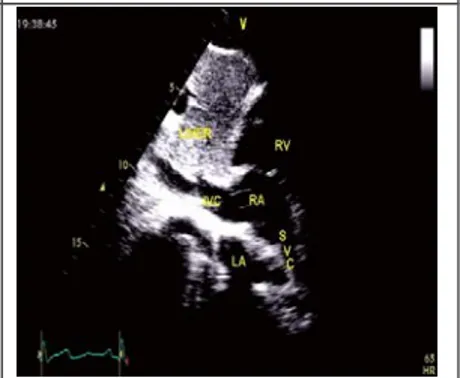

剑突下四腔心切面

探头位置:探头位于剑突下声速指向左肩。

观察内容:4个房室腔;二尖瓣、三尖瓣、房间隔、室间隔。

剑突下两房切面

探头位置:剑下四腔心切面调整声速指向患者的右后背侧。

观察内容:上下腔静脉入右房的入口、左房、右房、房间隔。